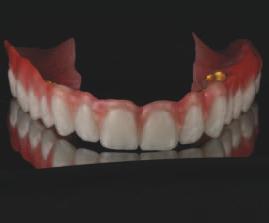

În cazul de față, s-a pro ectat o nouă setare restaurat vă folos nd ca refer nță restaurăr le ex stente ale supraprotezelor. Noua setare a fost apo t păr tă folos nd o mpr mantă 3D. Un f ș er separat a fost exportat d n so ware, ceea ce a perm s mpr mante să t părească baza folos nd răș nă transparentă. Setarea dentară t păr tă a fost l p tă pe baza transparentă. Această nouă setare a fost testată în cav tatea orală. S-a evaluat relaț a d ntre zona cerv cală a setăr dentare ș creasta alveolară restantă. De asemenea, s-a determnat neces tatea une componente roz a restaurăr lor f nale (f g. 7).

7. Configurația nouă a restaurării a fost imprimată în 3D într-un fișier divizat: unul pentru baza protezei și altul pentru dinți. Acest lucru a permis medicului să utilizeze rășină transparentă la bază pentru a determina relația

dintre dinți și creasta edentată și necesitatea utilizării componentei roz în proteza finală. 8, 9. Ghidul chirurgical maxilar a fost construit să fie susținut de țesut și retenționat de ace de fixare. Configurația restaurativă a fost utilizată

pentru a asigura poziția implantului într-un mod ghidat restaurativ.